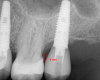

Fig 4. 2 mm is the distance lingually between the restorative platform and the buccal-gingival margin.

Figure 4

The next number is "2," which also refers to the distance between the restorative platform and the buccal-gingival margin, but for how far lingual the platform should be from the margin (Figure 4). With this measurement, similarly, it is better to err on the side of slightly greater than 2 mm as long as the trajectory of the implant is maintained to allow the screw access to come out of the central fossa. Too short a distance could result in an implant that has too little or no bone at all around the facial aspect of the implant. Such a situation would run the risk of having recession and ultimately even exposure of the implant and unpleasing long-term esthetics.